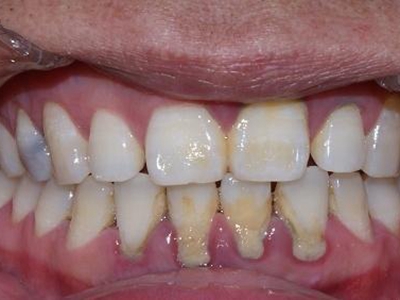

牙龈退缩露出淡黄色牙根图

牙龈退缩患者的牙龈退缩后,淡黄色牙龈明显露出。若进一步发展,易使对应位点的牙槽骨发生骨吸收,可能诱发龋齿、牙龈敏感、菌斑堆积等。